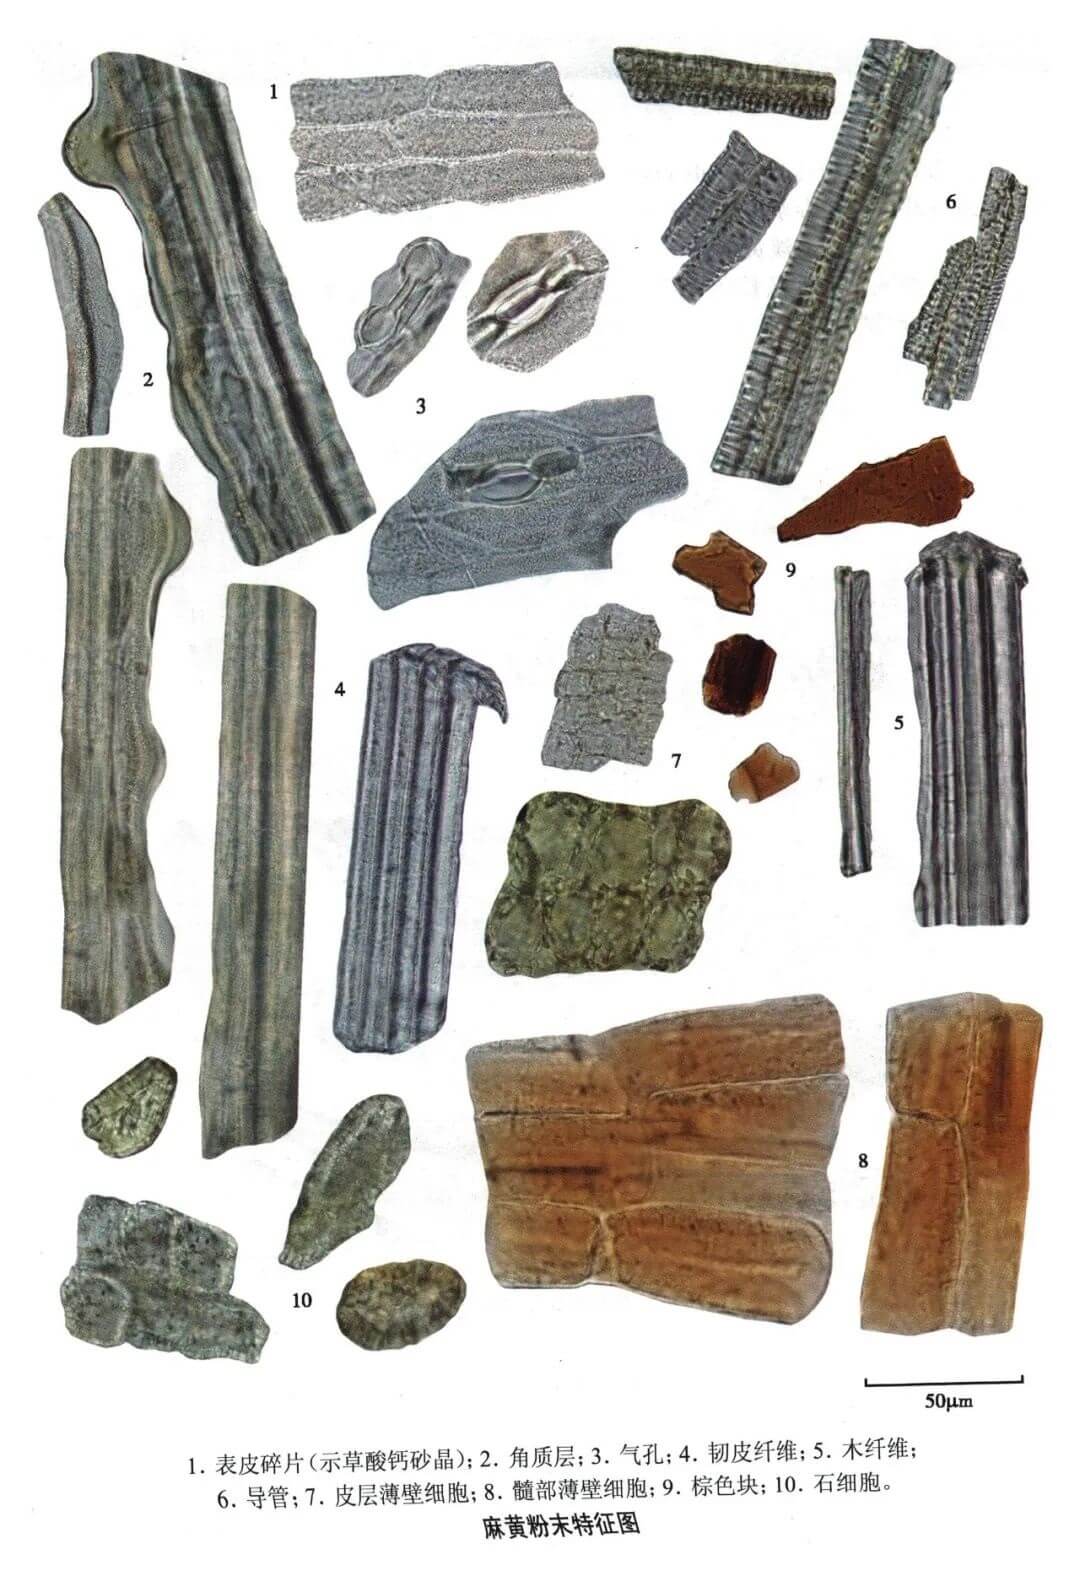

| 【显微鉴别】 草麻黄粉末。表皮组织碎片甚多,细胞呈长方形,含颗粒状晶体;气孔特异,内陷,保卫细胞侧面观呈哑铃形或顶面观呈电话听筒形。角质层极厚,呈脊状突起,常破碎呈不规则条块状。纤维多而壁厚,木化或非木化,狭长,胞腔狭小,不明显,附有细小众多的砂晶和方晶。皮层薄壁细胞呈类圆形,壁薄,非木化,含多数细小颗粒状结晶。⑤棕色块散在,棕色或红棕色,形状不规则。 |

| 【显微重点】 表皮组织含颗粒状晶体;气孔、嵌晶纤维。 |

| 【图谱来源】 《中药成方制剂显微图典》 |